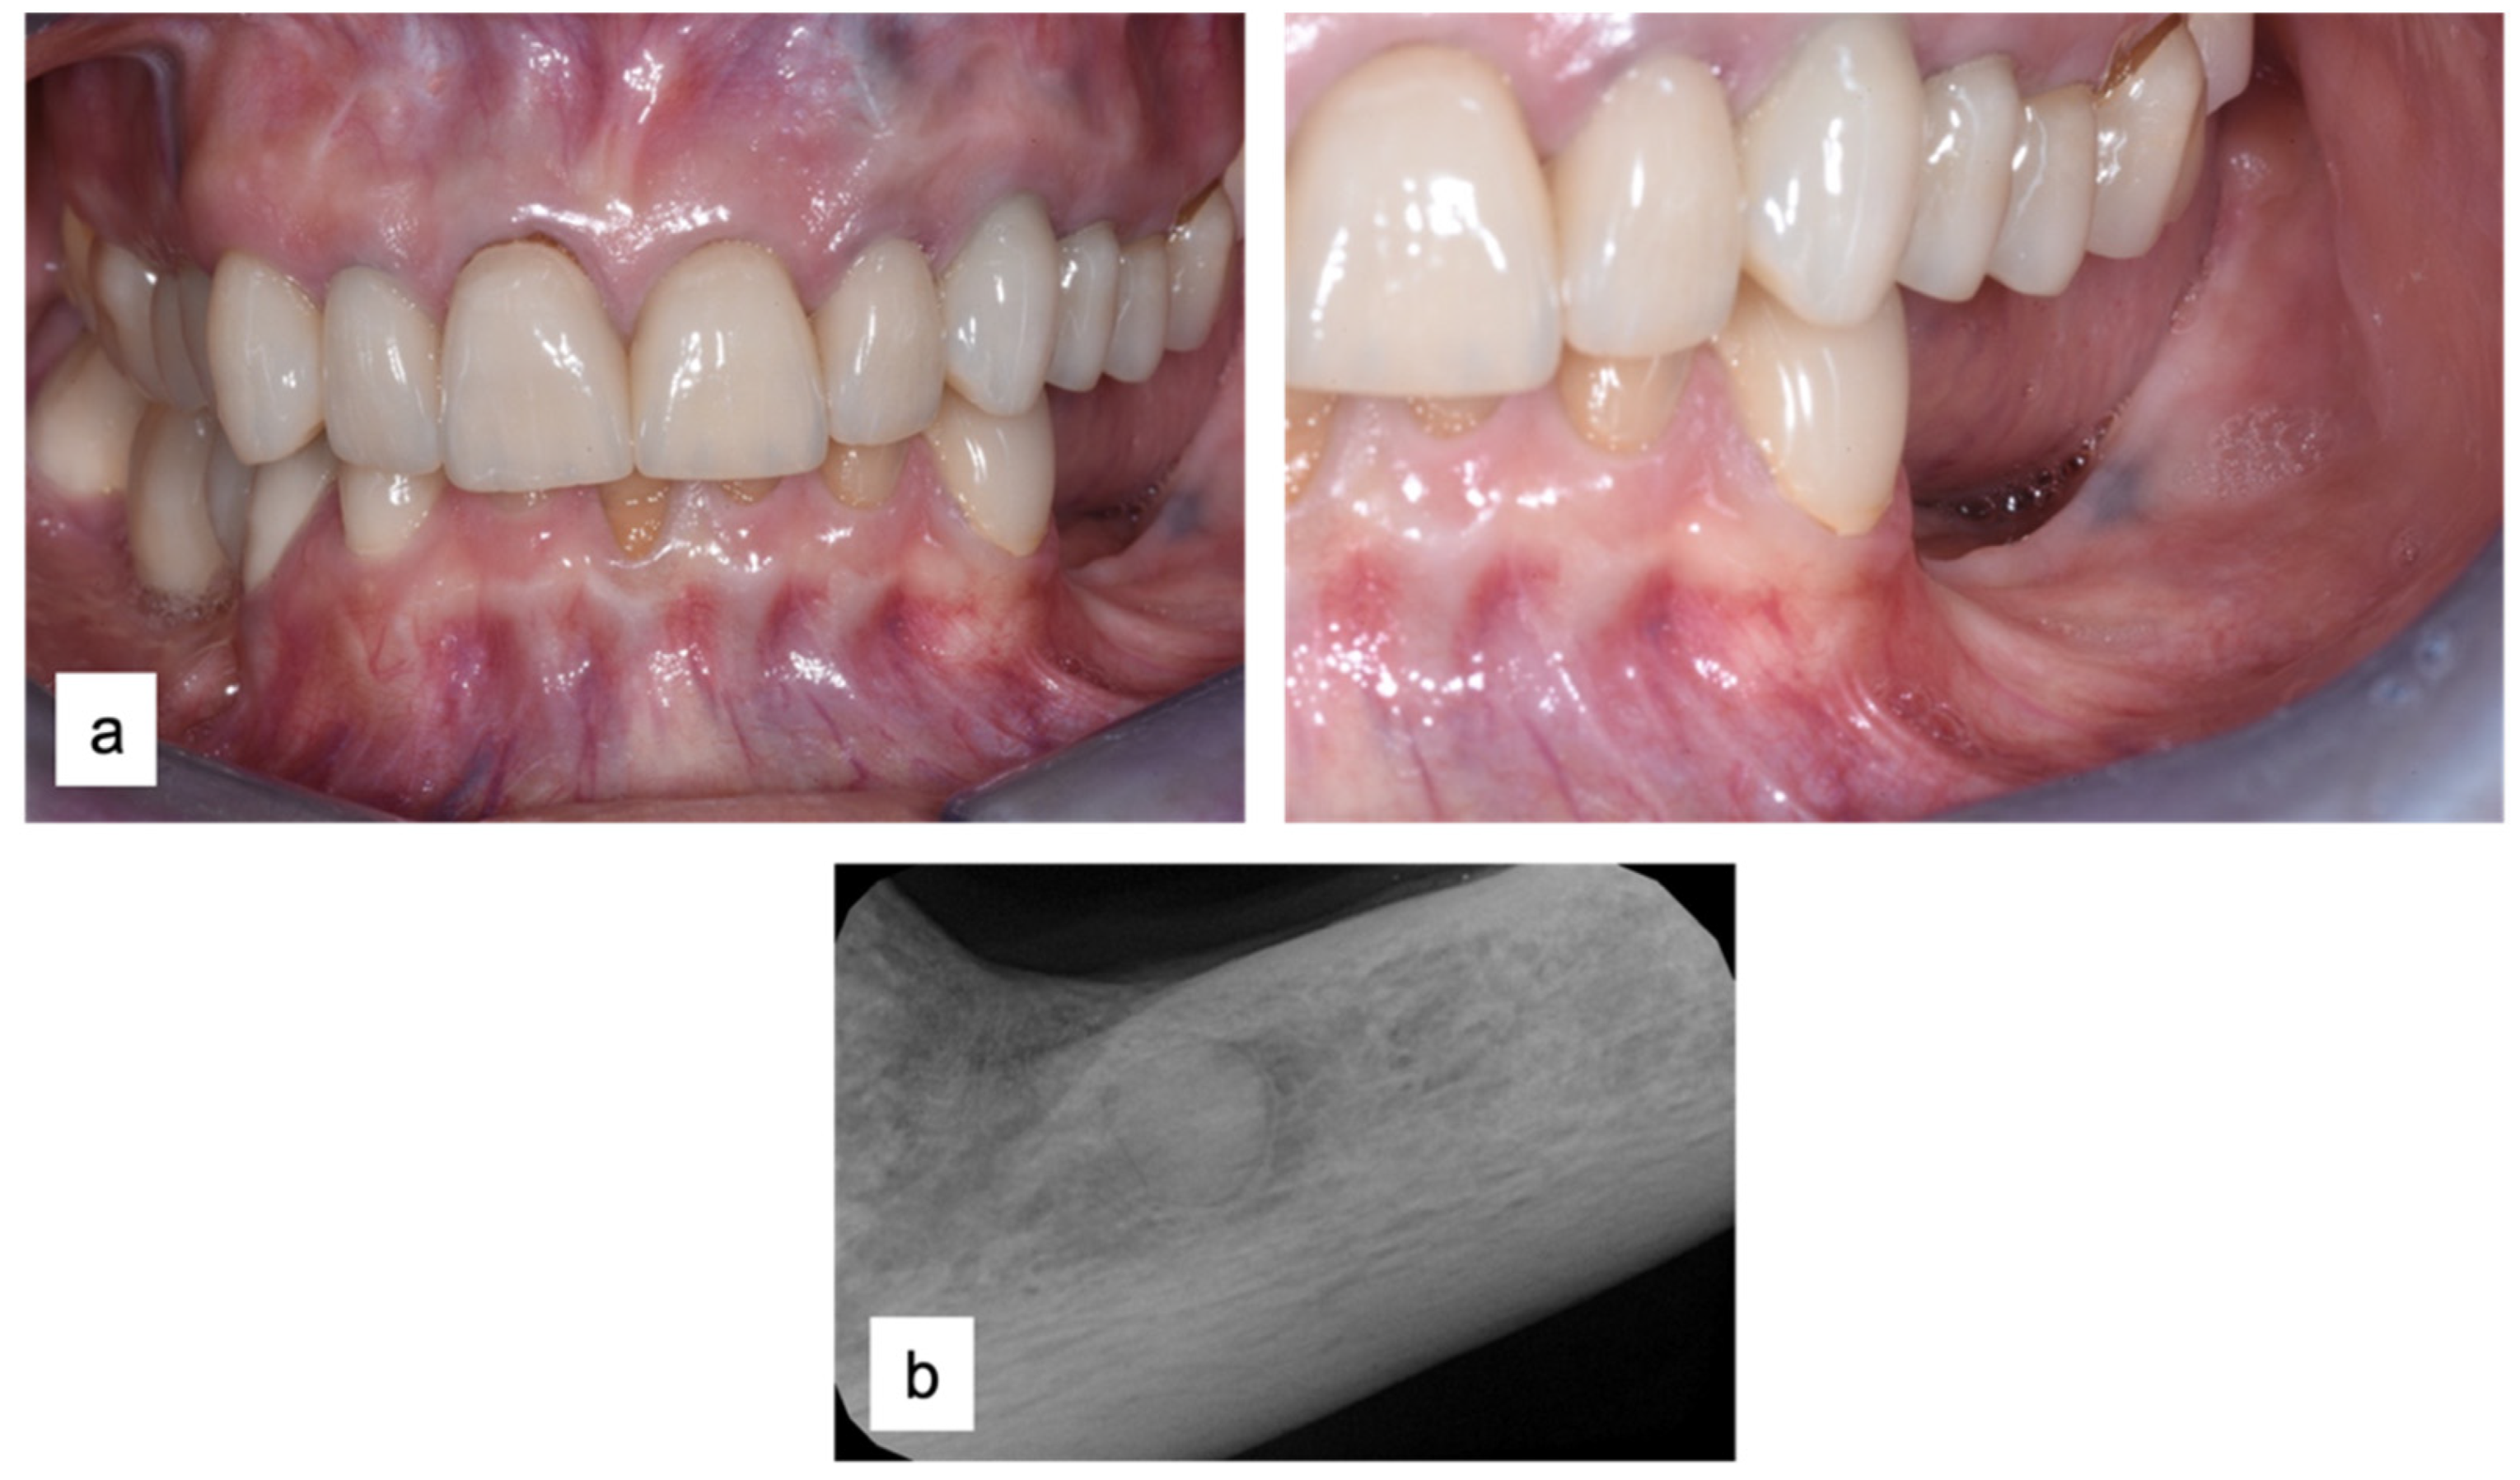

A 61-year-old female patient came to our attention. The clinical evaluation revealed a severe atrophic ridge in the left posterior mandible (Figure 2a). The patient stated that the teeth were extracted 5 years before and the first bicuspid only a month before the consultation. The radiographic evaluation showed the presence of a residual root fragment (Figure 2b). It was also possible to observe the radiolucency of the healing socket of the first bicuspid. The patient was further evaluated with a CBCT to complete the case documentation and data collection. The CBCT showed a severely atrophic ridge with an unfavorable anatomy for dental implant insertion (Figure 3).

Figure 2.

Consultation visit: (a) clinical evaluation at baseline; (b) periapical radiograph revealed the presence of a residual fragment of the root.